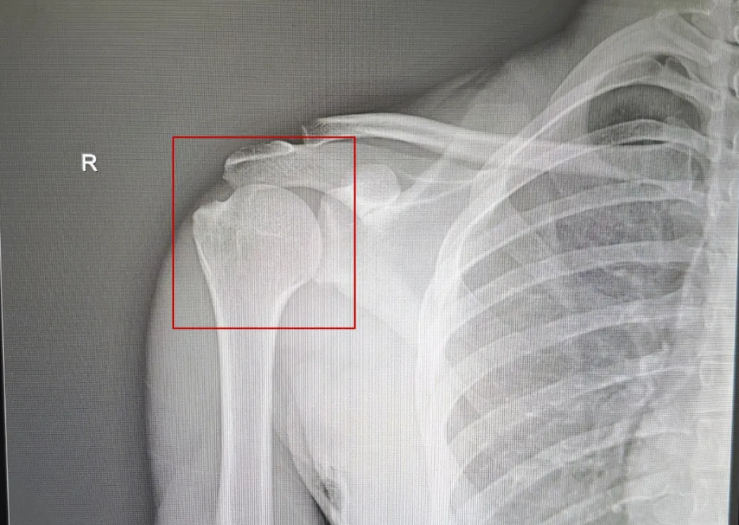

4月14日晚,和佳医院急诊科接诊 从外院慕名而来的外国留学生阿强(化名), 此时的他左手托着垂下来的右手手臂, 已经疼得说不出话来。 急诊科主任王超鹏迅速进行专科查体: 右肩呈“方肩”、关节弹性固定, 未发现畸形肿胀、骨摩擦感, 排除骨折因素后, 诊断为右肩关节前脱位。 王超鹏主任为患者进行专科检查 看到阿强因为疼痛汗泪连连, 王超鹏主任随即采用创伤更小、 更温和的“外旋法”进行复位。 王超鹏主任不到1分钟实现手法复位 随着关节归位,阿强肩部疼痛快速缓解, 连连点头惊叹称赞:“amazing!” DR显示:脱臼的右肩关节成功复位 夏季是运动损伤高发期, 此时运动损伤率比春秋季高30%! 尤其是球类运动这类高强度对抗 讲究策略,急停变向, 更是运动损伤的“重灾区”。 TIPS 关于运动健身 急诊医生有话说 苏超、苏BA等球类联赛开启,掀起全民运动健身的热潮。和佳医院急诊科王超鹏主任提醒: 1. 运动前务必充分热身,重点活动肩、膝、踝等关键关节,放松肌肉,降低关节脱位、拉伤风险; 2. 合理把控动作幅度,避免暴力冲撞与超负荷发力,做好护具防护; 3. 若突发关节错位、扭伤、磕碰疼痛,一定不要盲目拉扯、强行活动,及时制动休息(停止运动、立即休息); 4. 急性运动损伤时,第一时间前往医院就诊,明确排查骨折、韧带损伤,接受专业复位与对症治疗,避免二次损伤。 和佳医院急诊科提供24小时诊疗服务,畅通医疗救治绿色通道,整合骨科、脑科、心内科、普外科、泌尿外科、影像科等多学科力量,处理各类运动损伤、意外创伤,并开展超减张美容缝合技术。以专业诊疗能力,为运动爱好者的健康保驾护航。